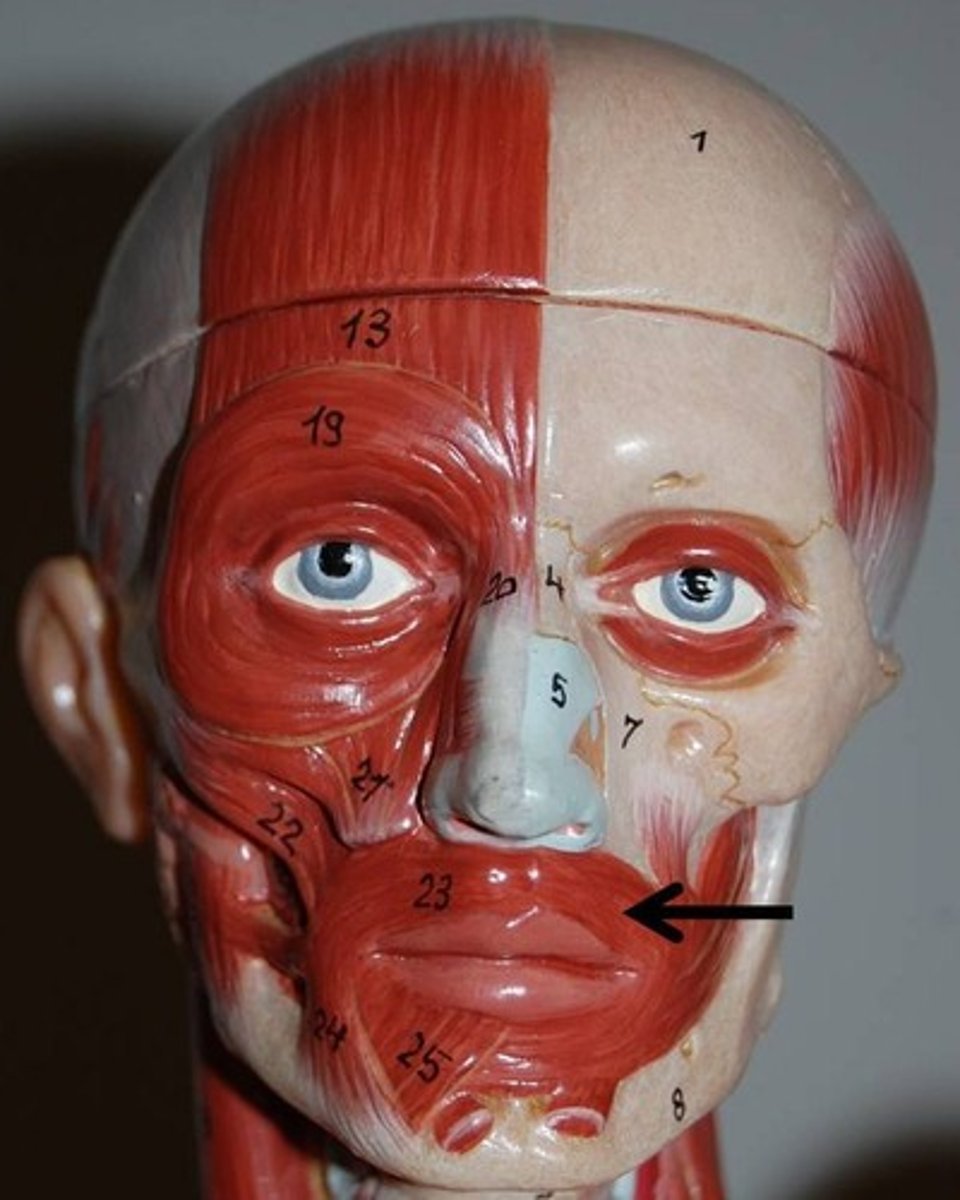

Orbicularis Oris

Consists of numerous strata of muscular fibers surrounding the orifice of the mouth, but having different direction